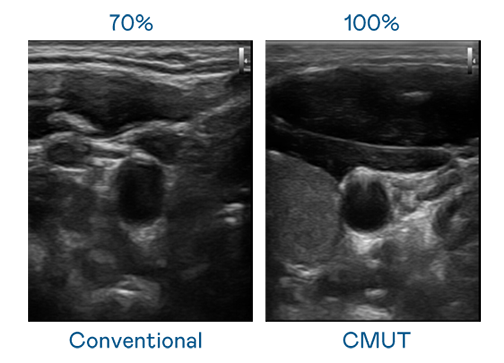

CMUT 技术是一种用电容式微机电元件来产生超音波讯号的技术。与传统 PZT 压电式技术相比,CMUT 频宽增加 30%,更宽频的超音波讯号让影像解析度大幅提升,是实现高影像品质医疗超音波扫描、促进精准医疗发展的关键技术。

超音波影像的解析度高低,首先取决于探头能发出的讯号频宽。rb88随行版 CMUT 可提供高清晰的超音波讯号,提供高频宽、高灵敏度、影像纹理细节更高的超音波影像,协助医护人员缩短影像判读时间及利用精准的医疗影像进行诊断。